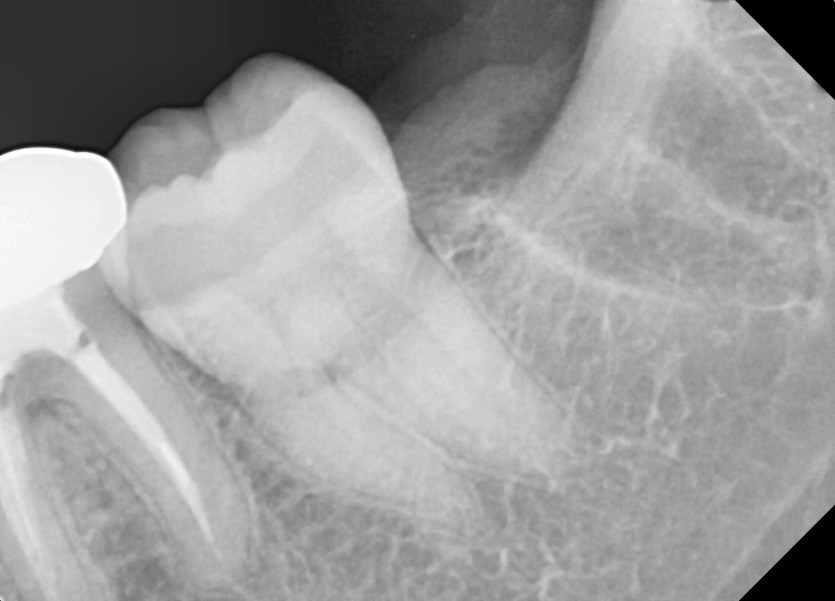

#28,38 사랑니 발치

구강 외과 전문의가 당일 발치했습니다.